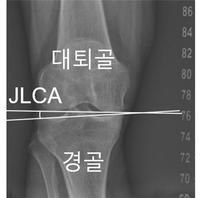

무릎 관절을 이루는 뼈가 벌어진 정도인 ‘관절선 수렴각(JLCA)’이 무릎 관절 변형을 가속화하는 결정적 지표라는 연구 결과가 나왔다.무릎 퇴행성 관절염은 국내 65세 이상 노인 10명 중 약 4명이 앓고 있는 대표적 만성 질환이다. 관절염의 진행에 영향을 미치는 주요 요인으로는 다리가 O자형(내반슬)이나 X자형(외반슬)으로 휘어 있는 ‘무릎 관상면 정렬’이 꼽힌다. 그러나 환자마다 무릎 정렬이 어떻게 변하는지, 그리고 어떤 환자에서 변형 속도가 급격히 빨라지는지에 대한 대규모 분석은 제한적이었다.서울대병원 정형외과 노두현 교수팀(분당서울대병원 강기수 전임의)은 2002년부터 2020년까지 환자들의 1만841개 다리를 평균 4년간 추적 관찰해 무릎 정렬 변화 양상을 분석했다.연구팀은 인공지능 기반 소프트웨어를 활용해 환자의 하지 엑스레이 사진을 분석했다. 이를 통해 엉덩이-무릎-발목 각도(HKAA), 관절선 수렴각(JLCA), 관절염 중증도(K-L 등급) 등 주요 지표를 측정했다. 다리가 휘어진 정도인 HKAA를 기준으로 하지를 ▲O자형 ▲중립 ▲X자형으로 구분하고, 정렬 변화가 연간 0.5° 이상인 경우를 ‘가속 진행’으로 정의해 정렬 변화 양상과 영향 요인을 분석했다.분석 결과, 무릎 정렬은 전반적으로 O자형 방향으로 진행되는 경향이 더 흔하게 나타났다. 특히 O자형 정렬 집단의 34.0%와 X자형 정렬 집단 25.7%에서 정렬이 빠르게 악화되는 가속 진행이 확인됐다.연구팀은 무릎 관절을 이루는 대퇴골과 경골 사이의 관절선이 벌어진 정도인 ‘관절선 수렴각(JLCA)’이 이러한 가속 진행을 예측하는 공통 지표임을 밝혀냈다. 초기에 측정된 JLCA가 1° 커질 때마다 O자형 환자에서 12.9%, X자형 환자에서 19.4%씩 가속 진행 위험이 증가했다. 특히 O자형 환자의 경우 관절염 중증도가 높을수록 가속 진행 위험이 증가했으며, 중등도 이상(Grade III, IV) 단계에서는 정상군(Grade 0) 대비 약 4~5배 높은 것으로 나타났다.노두현 교수(정형외과)는 “이번 연구를 통해 엑스레이 사진에 인공지능 기술을 결합함으로써 MRI 없이도 향후 관절염의 변형 위험을 예측할 수 있는 가능성을 확인했다”며 “환자별 무릎 정렬 변화 양상을 정량적으로 제시해 더욱 선제적인 맞춤형 치료가 가능해질 것으로 기대한다”고 말했다.강기수 전임의는 “세계 최대 규모의 분석을 통해 무릎 정렬이 빠르게 악화되는 환자군의 특징을 확인했다”며, “이는 임상 현장에서 관절염의 가속 진행을 예측하고 대비하는 중요한 단서가 될 것”이라고 했다이번 연구 결과는 국제 학술지 ‘Knee Surgery, Sports Traumatology, Arthroscopy (KSSTA)’ 최근호에 게재됐다.